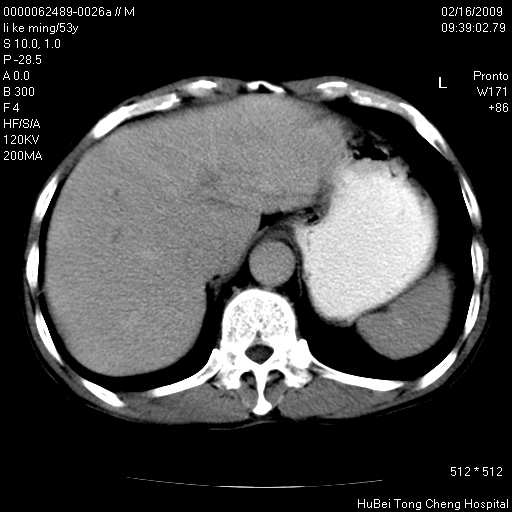

以下是引用卜一在2009-2-16 16:13:00的发言:[br]胰胆管扩张,末端明显狭窄 梗阻,胰头及十二指降段壶腹部结构紊乱。多考虑:十二指降段壶腹部癌!

以下是引用zsl6918在2009-2-17 8:48:00的发言:[br]符合胰头癌侵犯十二指肠。